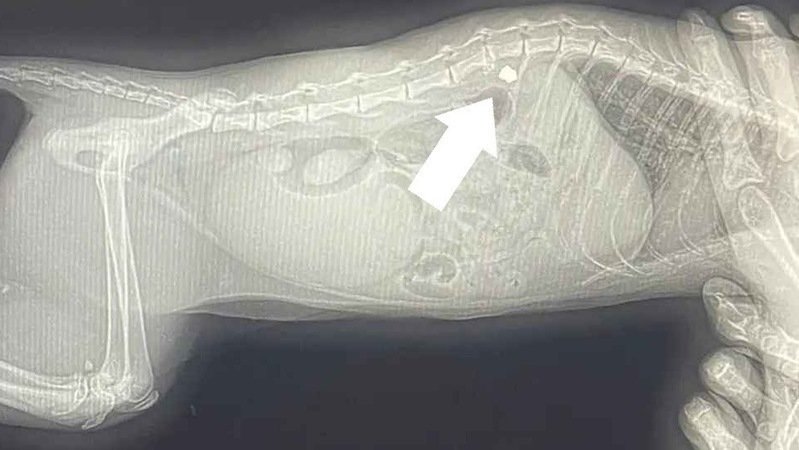

She was shot, her tiny body wracked with pain, as she lay helpless in a war-torn area of Ukraine still occupied by the Russian military.